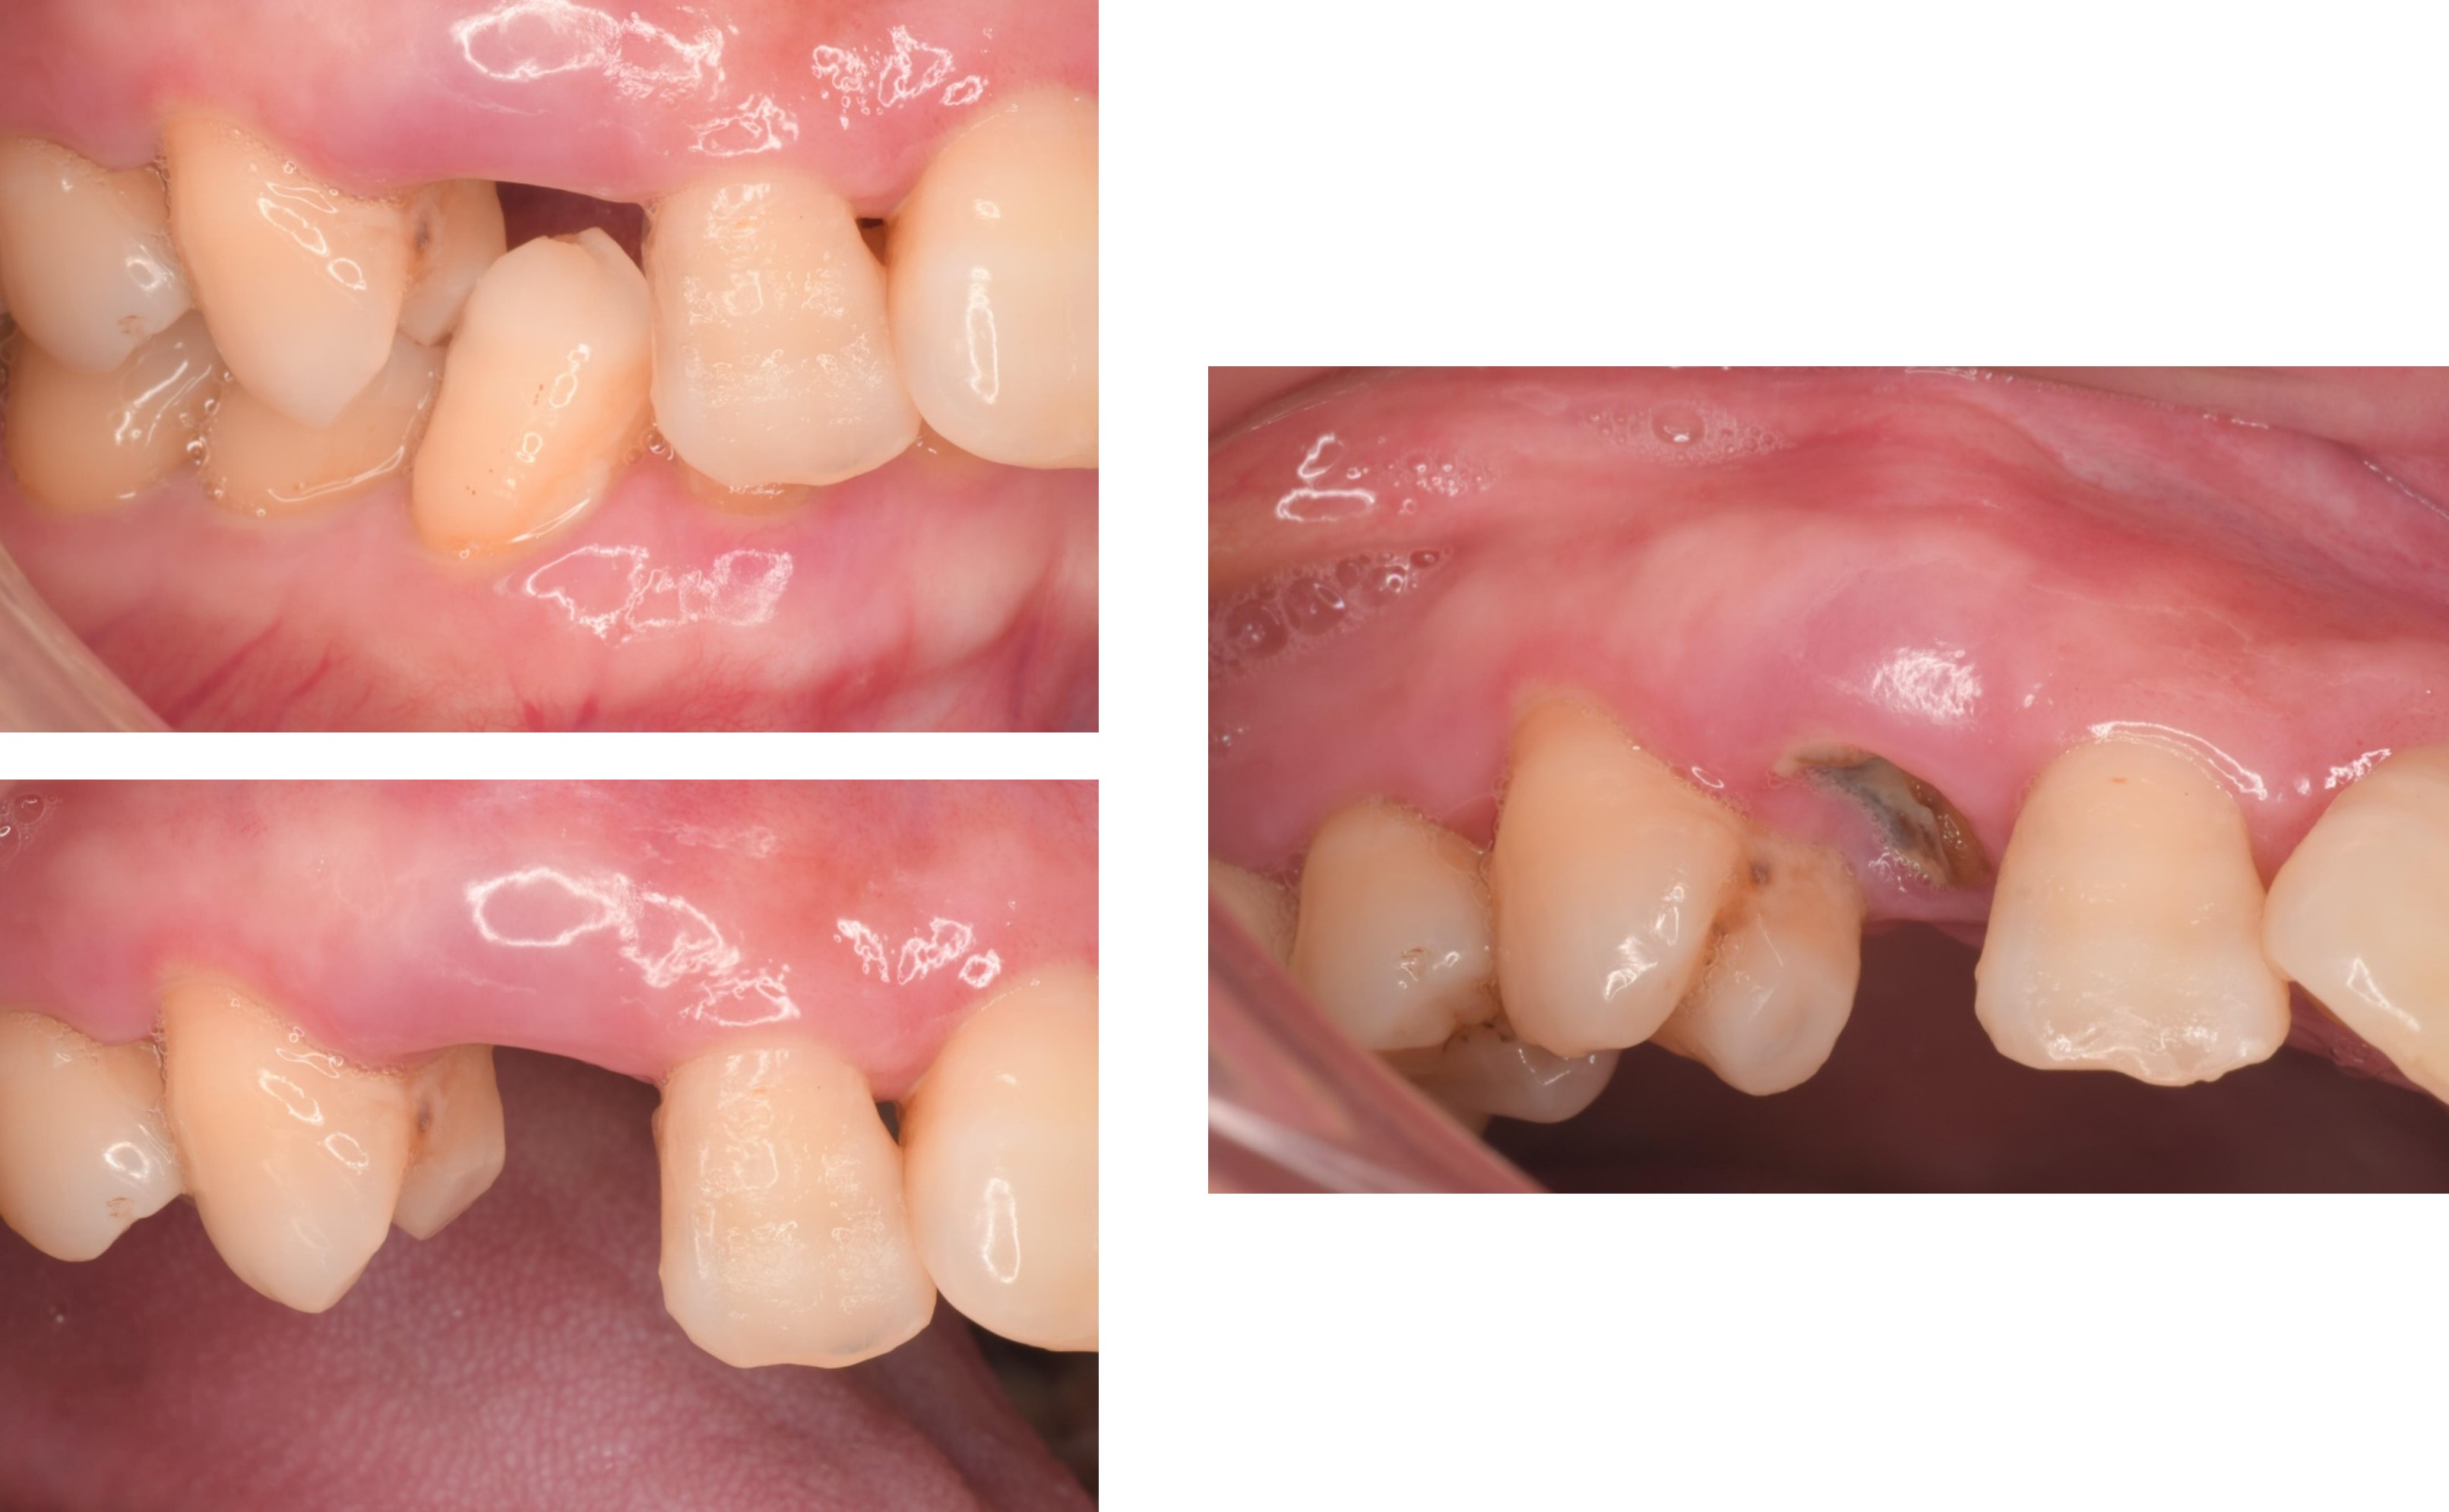

治療前,牙齒斷裂

治療前,牙齒嚴重斷裂